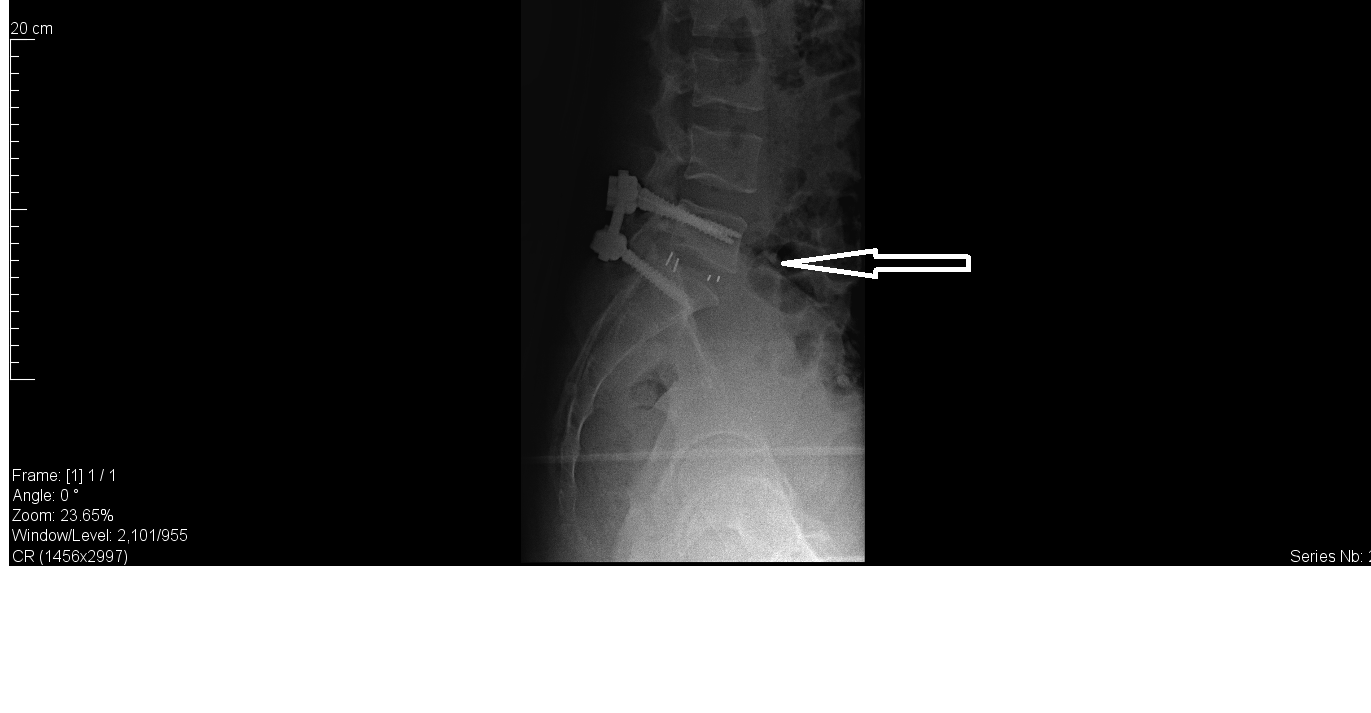

He was operated and managed with a laminectomy and discectomy at L5-S1 followed by posterior lumbar interbody fusion and trans-pedicular fixation at L5-S1 level with four screws.

| Postop X-ray |